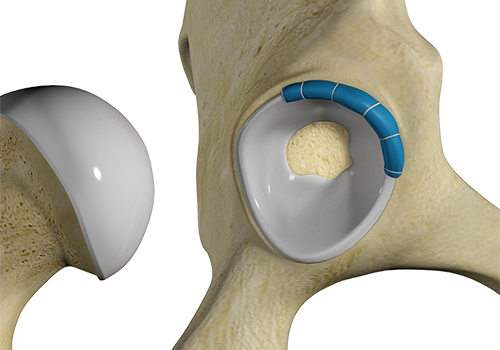

Total hip replacement is a surgical procedure in which the damaged cartilage and bone are removed from the hip joint and replaced with artificial components. The main indication for total hip replacement is arthritis.

Hip replacement surgery is one of the most common orthopedic surgeries performed. It involves the replacement of the damaged hip bone (ball shaped upper end of the femur) with a ceramic ball attached to a metal stem that is fixed into the femur and placing a new cup with a special liner in the pelvis.

The hip is a ball and socket joint comprising of the femur (thigh bone) and the pelvic bone. The head of the femur (ball) articulates with a cavity (socket) called the acetabulum in the pelvic bone.